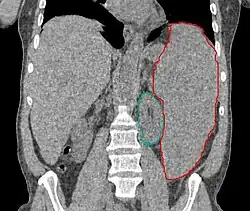

Znacznie powiększona śledziona (zaznaczona na czerwono, na zielono zaznaczono nerkę) w tomografii komputerowej | |

Niekiedy występuje hepatomegalia, splenomegalia lub limfadenopatia (powiększenie węzłów chłonnych).